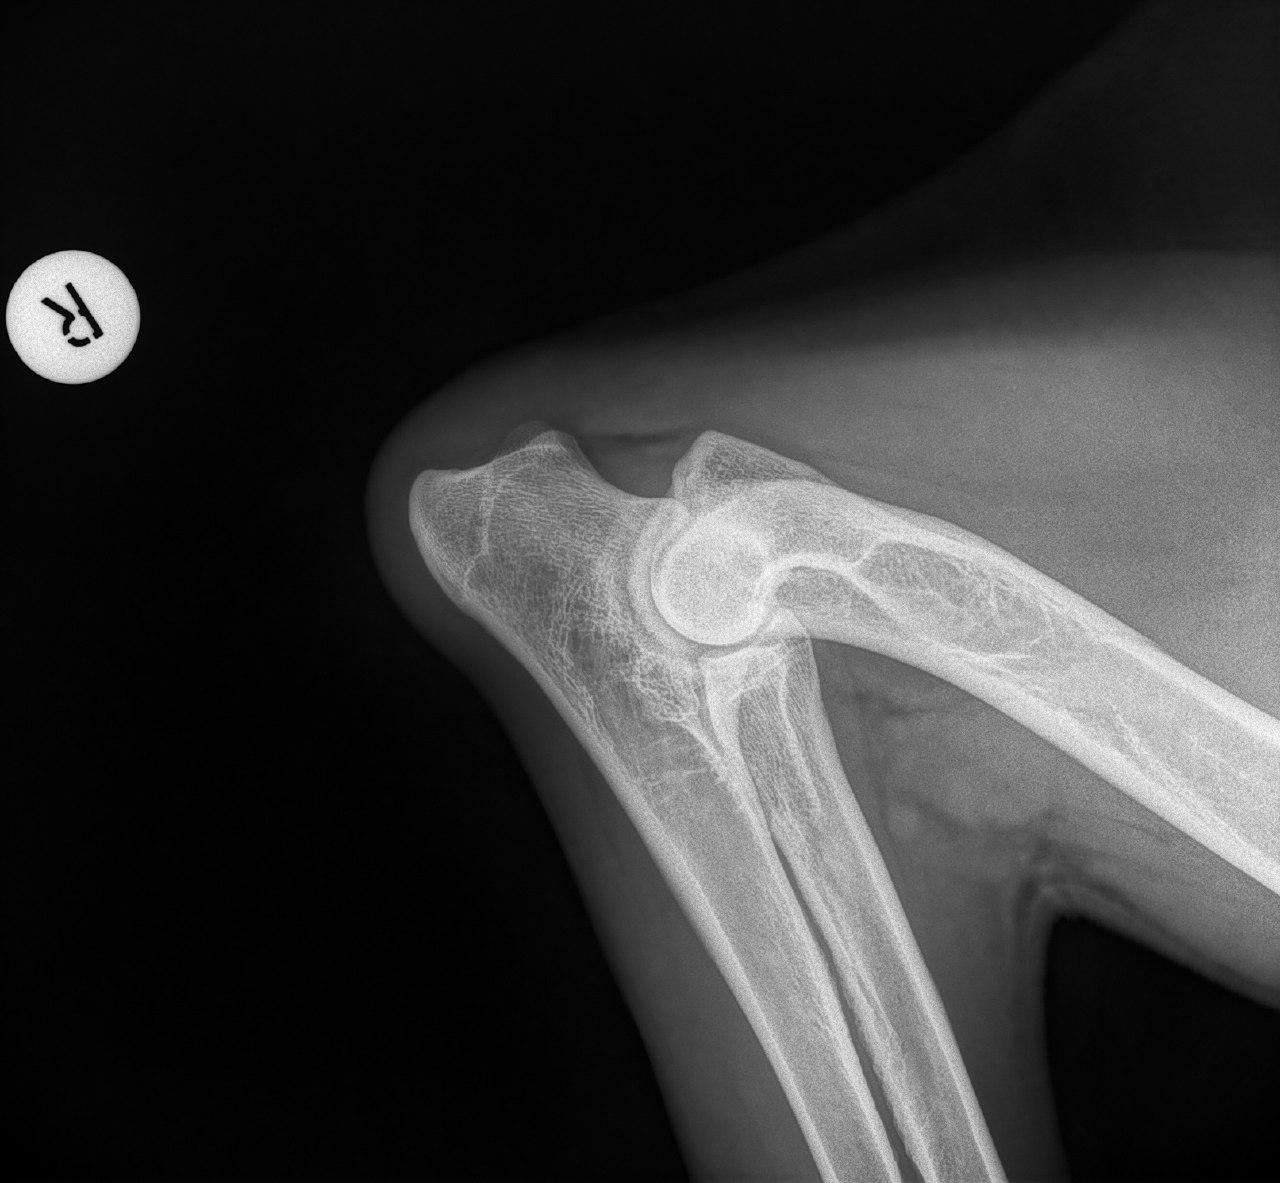

Wir haben zwar keine hd aber der Chirurg der unsere ed operiert hat hat es mir klipp und klar erklärt.

Meiner hat schwere ed rechts...im Stammbaum gibt es lediglich einmal beim Opa "ed fast normal " und trotzdem hat er sie.

Mit der HD ist das so ne Sache..... die Vererbung spielt eine sehr große Rolle, ja. Aber bei unserer Peggy Zb ist es so, dass mehrere Generationen nachweislich HD und ED frei sind und auch frei von Spondylosen. Als einziger Hund überhaupt in der gesamten Zucht hat unsere Dame alles mitgenommen, was zu kriegen war;(: sie hat nicht nur schwere HD, weil ihre Hüfte viel zu locker ist, sondern dadurch bedingt am rechten Knie bereits schwere Arthrose und hinten links eine Sehenschwäche (durch Überlastung), weshalb sie dort durchtrittig ist. Und als würde das alles nicht schon vollkommen reichen, wurden aktuell auch noch mehrere heftige Spondylosen diagnostiziert;(. An einer Stelle ist sogar schon etwas abgebrochen8|.